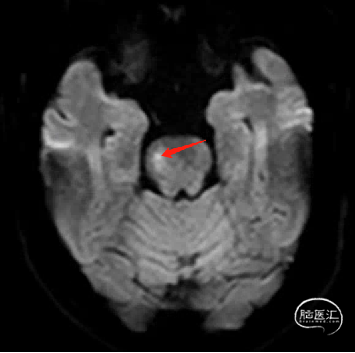

现病史:患者14天前因“左侧肢体乏力伴言语不利14小时”就诊于当地医院,后转入我院完善MRI+MRA检查示:脑桥急性梗死,基底动脉近端动脉瘤。

术前MRI+MRA示:脑桥急性梗死,动脉瘤位于基底动脉近端,左侧椎动脉优势。